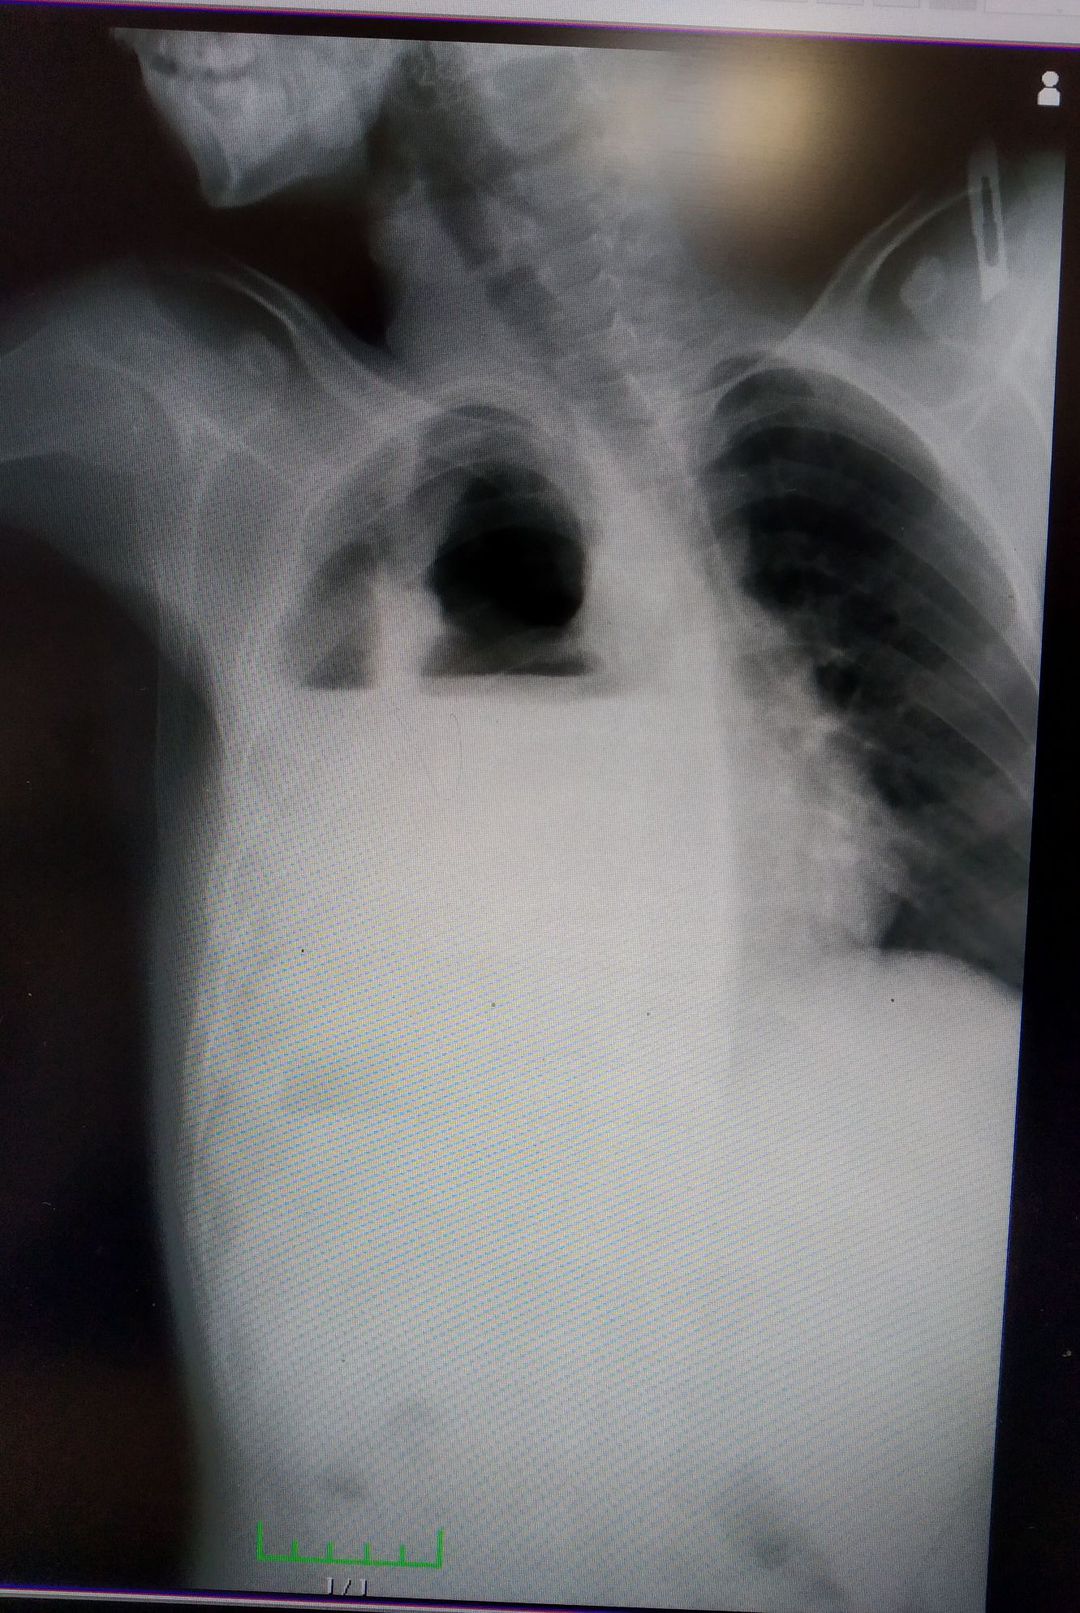

parapnomic pleural effusion

patient with dyspnea.saturation 84 percent.x-ray has air fluid level.tube thoracostomy was performed.